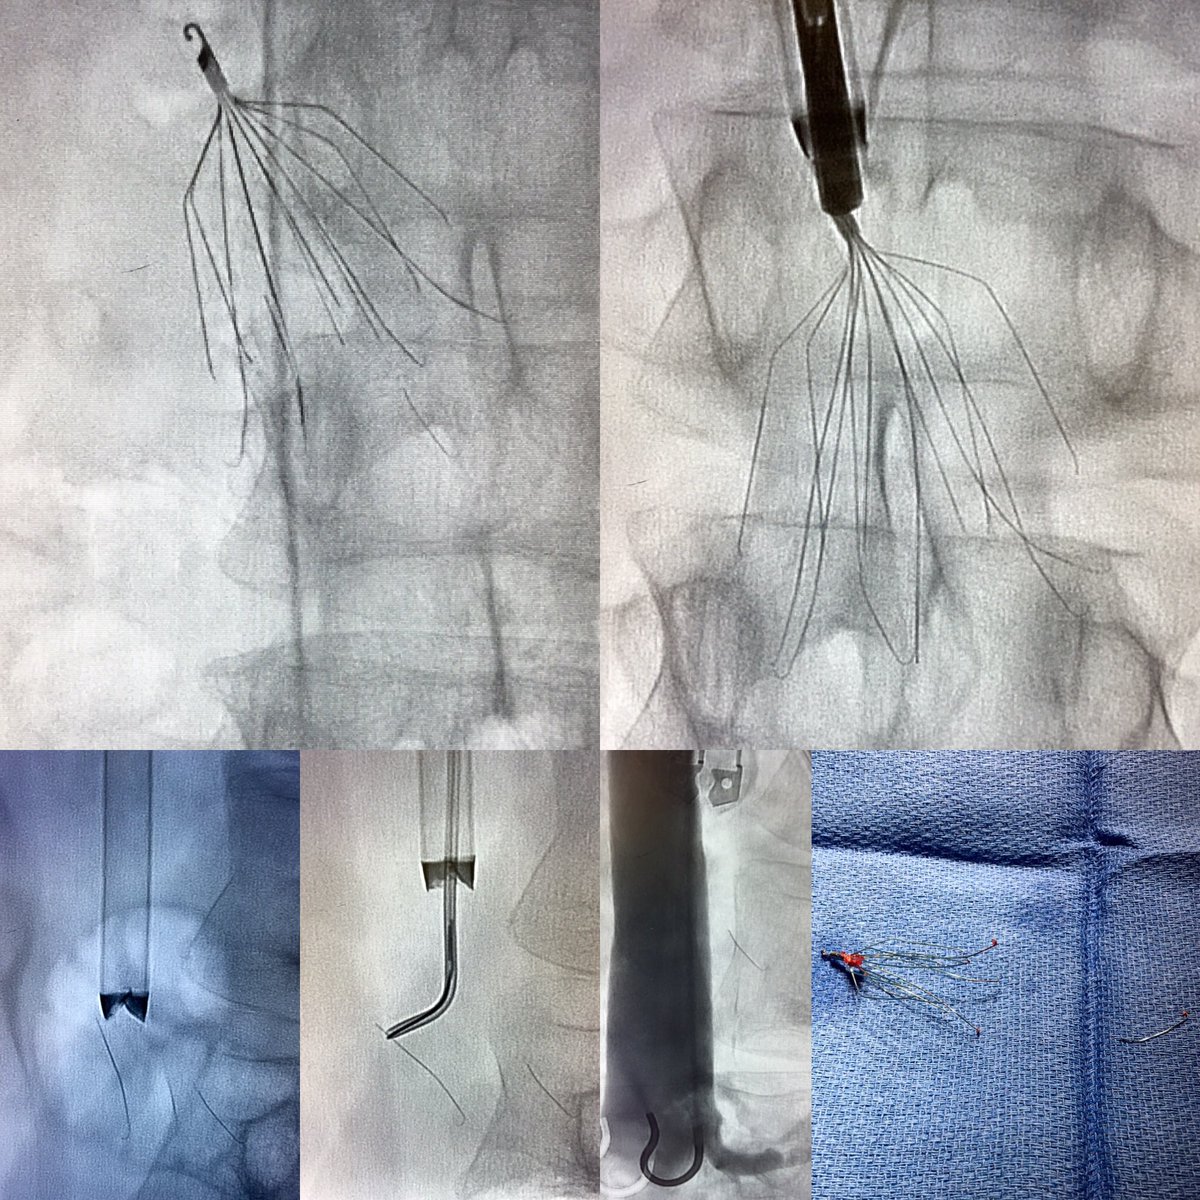

8 year-old Bard Meridian #filterOUT. Surrendered to Avantec’s Captus device. @rkryu @kush_r_desai @NorthwesternIR #iRad #GTFO

UCD_IR's tweet image. 8 year-old Bard Meridian #filterOUT. Surrendered to Avantec’s Captus device. @rkryu @kush_r_desai @NorthwesternIR #iRad #GTFO